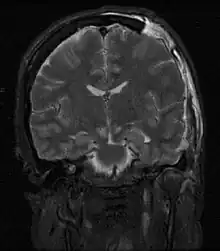

| MRI showing injury due to brain herniation | |

Treatment involves removal of the etiologic mass and decompressive craniectomy. Brain herniation can cause severe disability or death. In fact, when herniation is visible on a CT scan, the prognosis for a meaningful recovery of neurological function is poor.[2] The patient may become paralyzed on the same side as the lesion causing the pressure, or damage to parts of the brain caused by herniation may cause paralysis on the side opposite the lesion.[11] Damage to the midbrain, which contains the reticular activating network which regulates consciousness, will result in coma.[11] Damage to the cardio-respiratory centers in the medulla oblongata will cause respiratory arrest and (secondarily) cardiac arrest.[11] Investigation is underway regarding the use of neuroprotective agents during the prolonged post-traumatic period of brain hypersensitivity associated with the syndrome.[17]